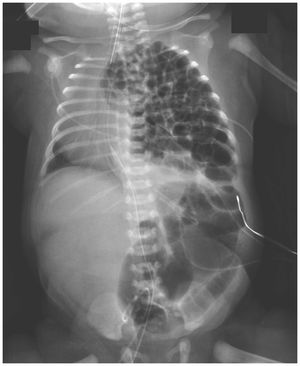

A female infant was delivered by planned cesarean section at 36 weeks of gestation because of a prenatal diagnosis of congenital diaphragmatic hernia. The neonate was intubated immediately after delivery. A nasogastric tube was inserted and suction begun to decompress the bowels to allow for better lung expansion. Chest radiography revealed multiple loops of bowel occupying the left hemithorax, which shifted the cardiothymic structures to the right. Congenital diaphragmatic hernia occurs when the diaphragm muscle fails to close during fetal development; the defect can occur on the right side, left side, or, on rare occasions, both sides. Defects on the right side, which manifest with the liver in the chest, are treated with diaphragmatic patch repair and are associated with higher rates of high-frequency ventilation, extracorporeal membrane oxygenation, and death than are defects on the left side. In our patient, the posterolateral diaphragmatic defect, also called a Bochdalek hernia, measured 3 cm by 4 cm, and because of the more favorable location on the left side, the defect was fixed surgically by primary repair on the third day of life. After the surgery, the patient received high-frequency ventilation but not extracorporeal membrane oxygenation. She was discharged home from the neonatal intensive care unit after 1 month and did well. However, the defect recurred 6 months later, and a second operation was performed. Jared Klein, M.D. Megan Sirota, M.D. Children’s Hospital of Richmond at Virginia Commonwealth University, Richmond, VA source: nejm.org